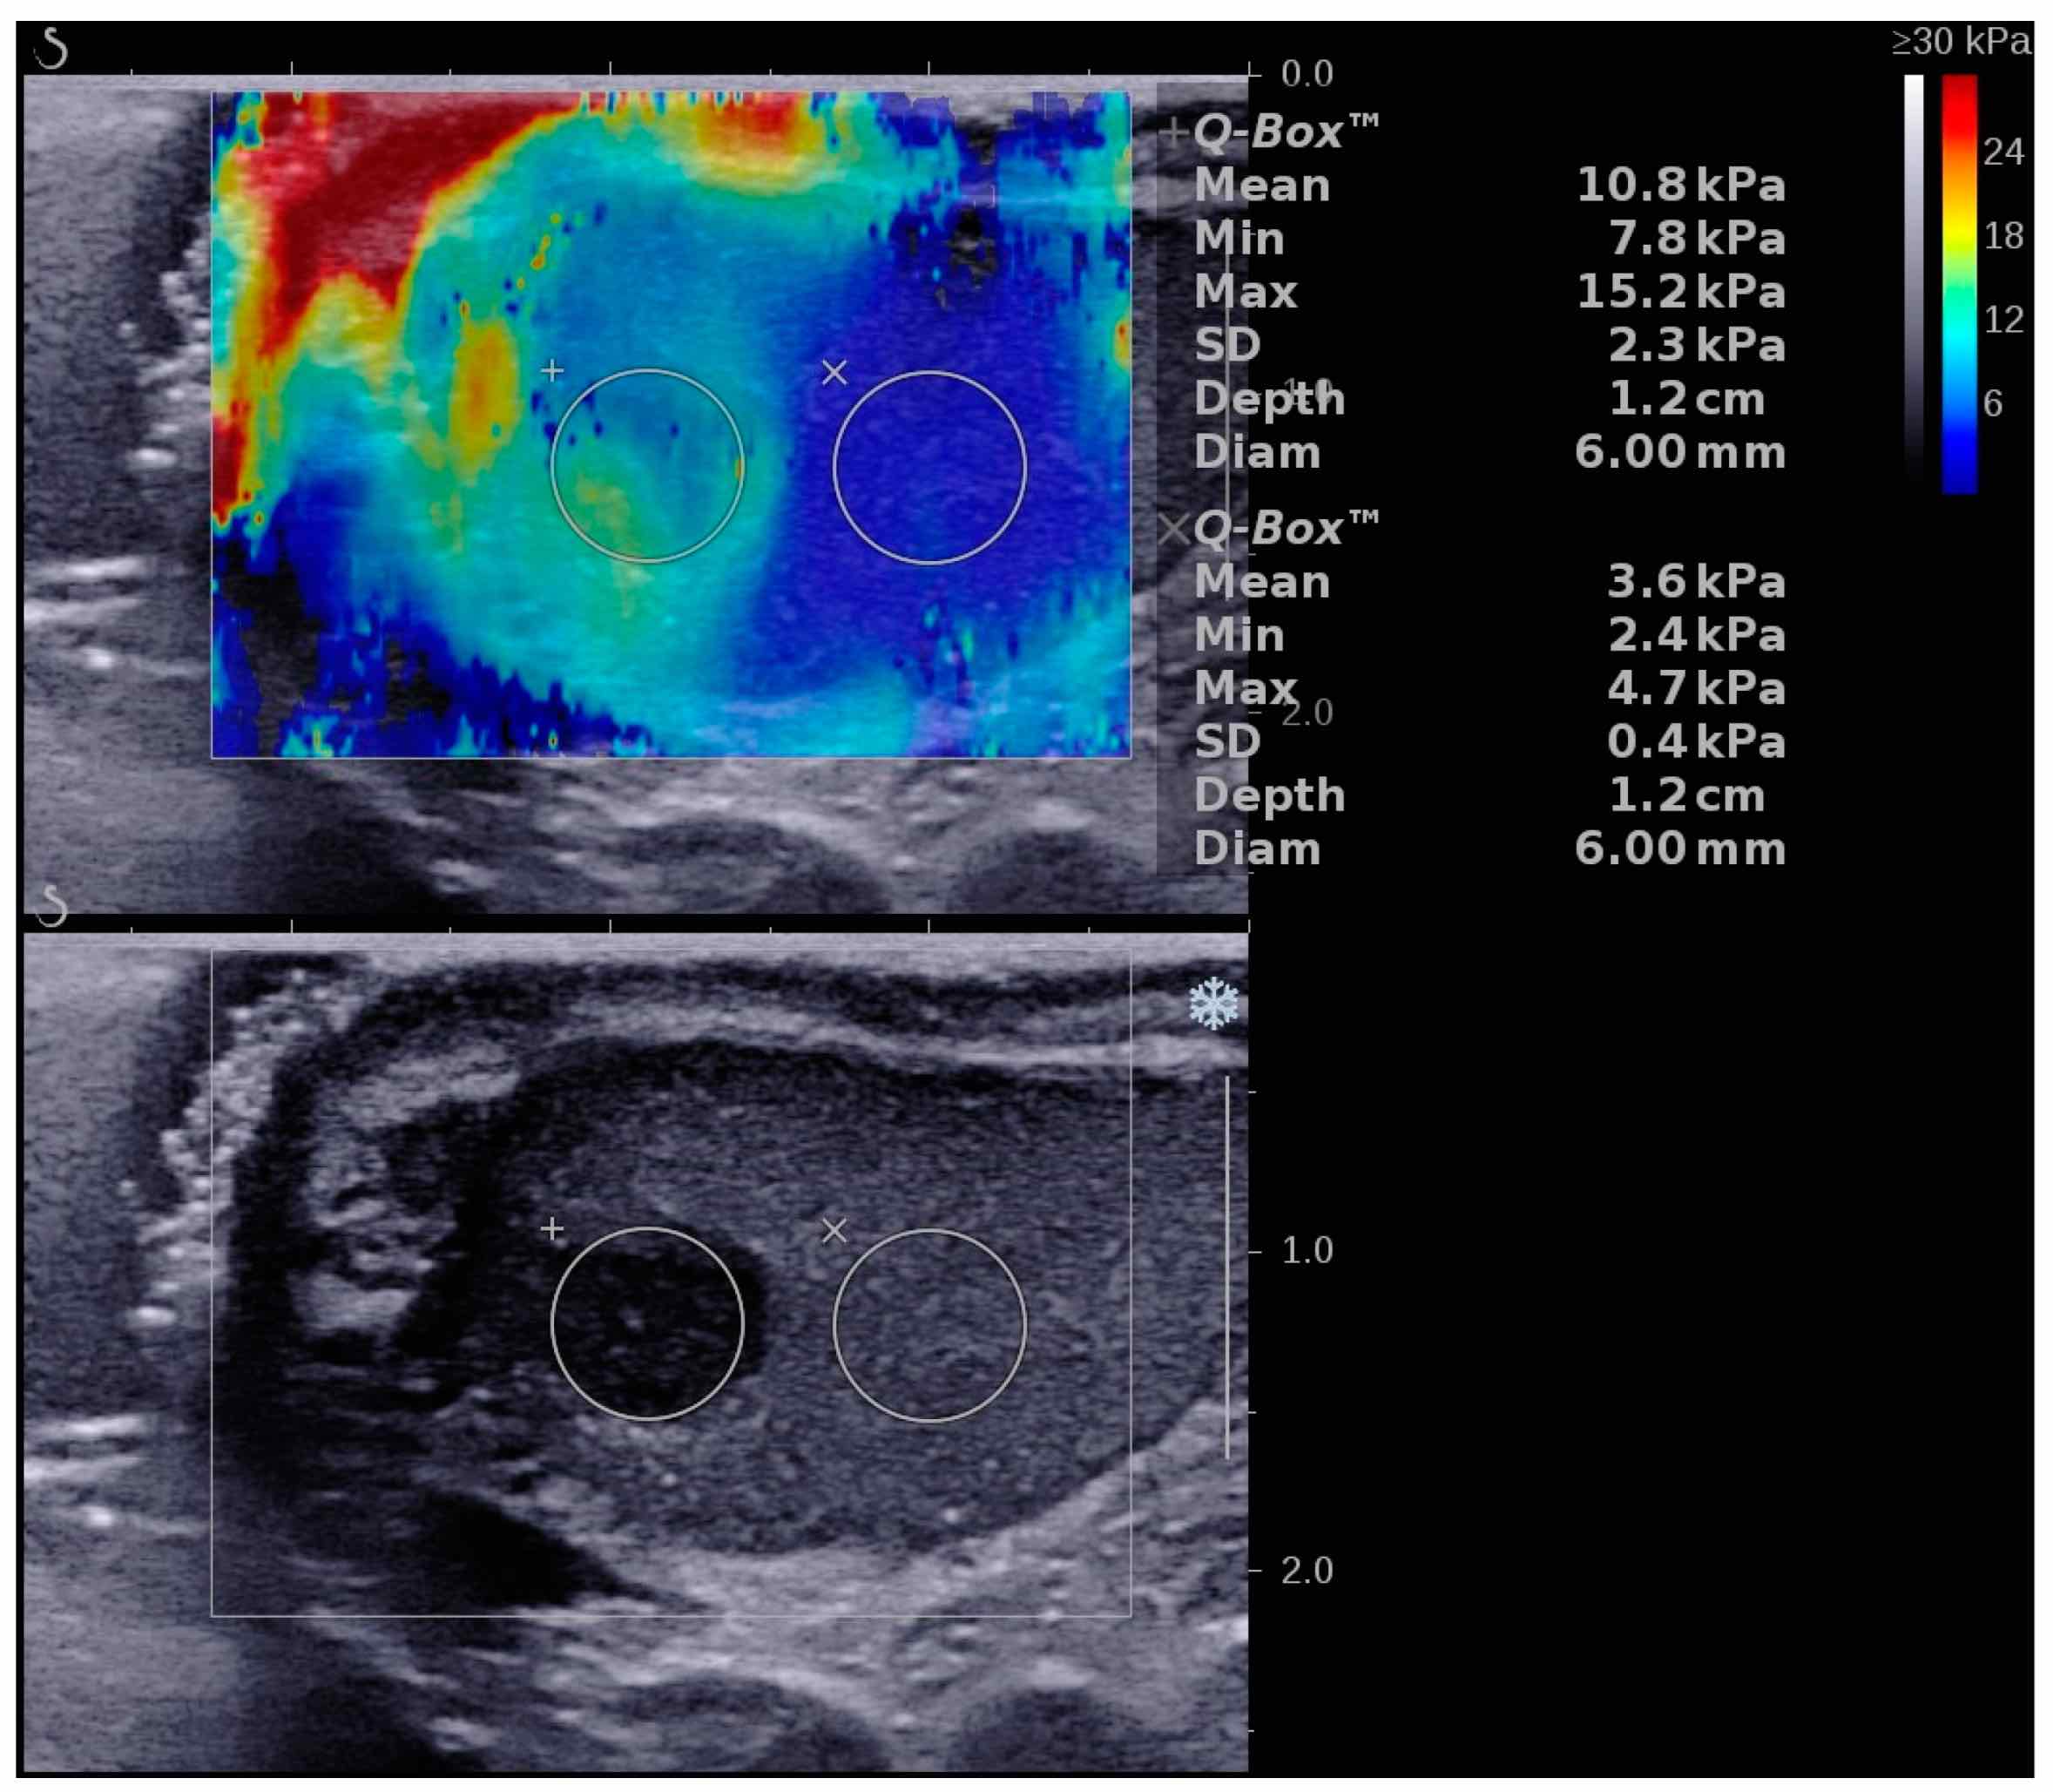

Еластографія